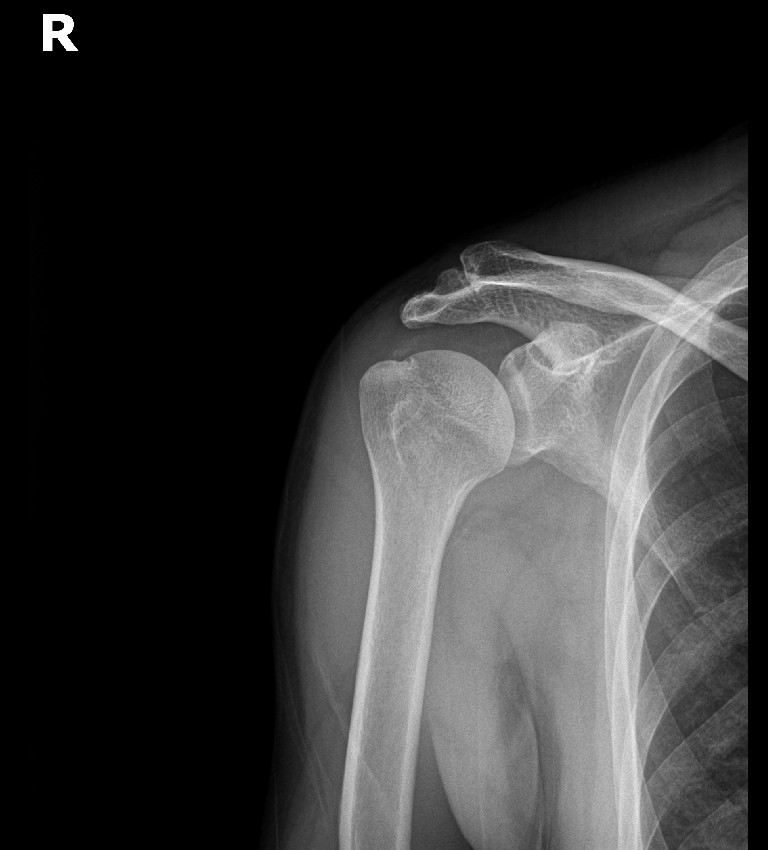

Step 6: 최종 확인 및 마무리

초음파와 X-ray로 석회 제거 확인 후 마무리합니다.

초음파: 석회 부위 확인

X-ray: 석회 완전 제거 확인

X-ray: 약 1.3cm 석회 (휴지기)

시술 직후 X-ray에서 석회 완전 제거 확인